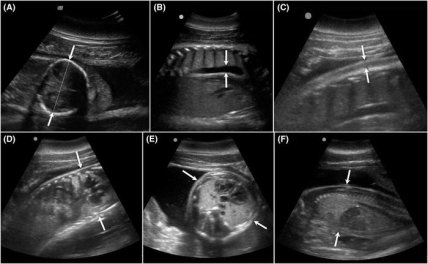

Модернизированный подход позволяет обнаружить аномалии и осложнения в развитии плода на всех стадиях беременности. "Эта передовая ультразвуковая технология позволяет нам диагностировать проблемы уже в первом триместре беременности у дельфинов", — отмечает Форест Гомес, директор по медицине Национального фонда по морским млекопитающим (NMMF).

С помощью того же метода исследователи могут оценить общее здоровье дельфина — точнее, его легочной, сердечной, печеночной, мочевыделительной, желудочно-кишечной и лимфатической систем. Для того, чтобы сделать тесты более комплексными, исследователи NMMF разработали последовательный протокол для ультразвукового мониторинга беременных дельфинов.

Несмотря на относительно небольшой размер выборки, в ходе исследования было проведено более 200 УЗИ-обследований и в каждом сканировании ученые нашли до 70 факторов, что позволило группе определить типичные проблемы, которые могут возникнуть как для плода, так и для самих дельфинов.